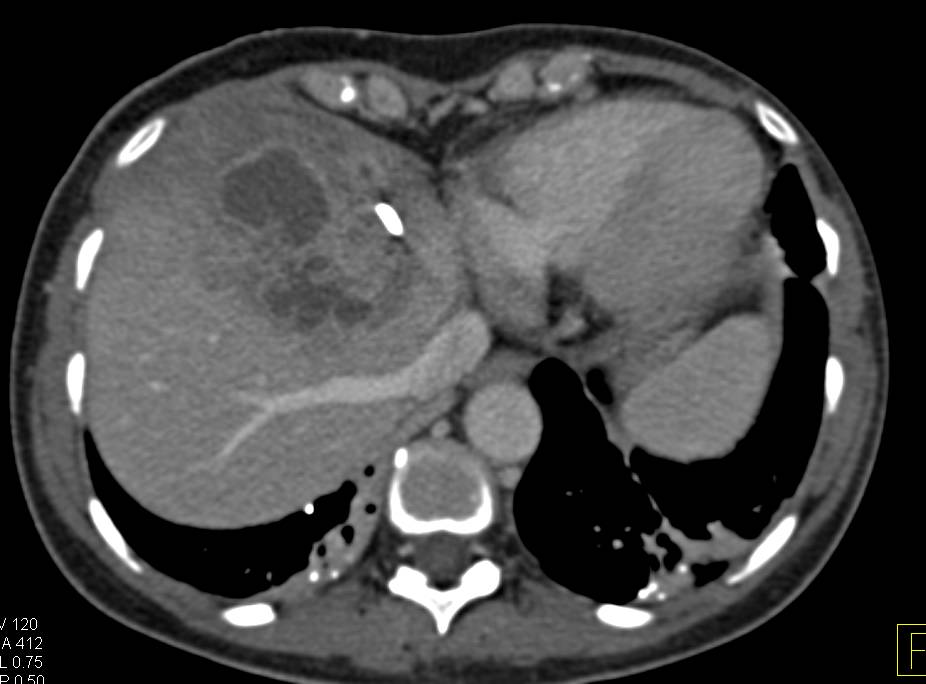

Фотографии и изображения, связанные с симптомами первичного склерозирующего холангита